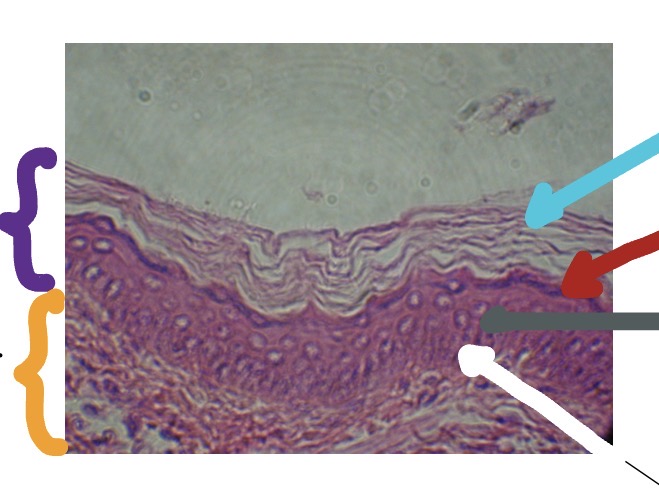

<p>What’s the purple line for this photo?</p>

Epidermis

<p>What’s the orange line for this photo?</p>

Papillary Layer of Dermis

<p>What’s is the blue line in this photo</p>

Stratum Corneum

<p>What is the red line in this photo</p>

Stratum Granulosum

<p>What is the grey line in this photo</p>

Stratum Spinosum

<p>What is the white line in this photo</p>

Stratum Basale